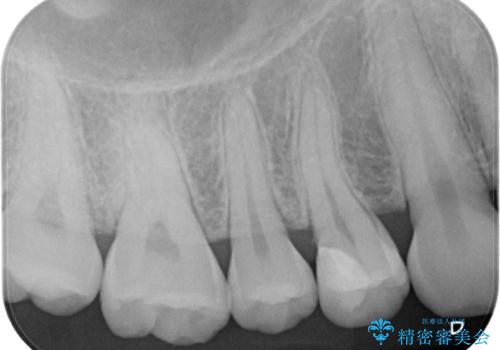

フロスの引っ掛かりやレントゲン像から、CRを除去し、虫歯を徹底的に除去し、精度の高いセラミックインレーにて修復することとしました。

虫歯が神経に近接している可能性があるため、念のためラバーダムをして虫歯の除去を行いました。

レントゲン像から、隙間のない精度の高い詰め物が入っていることが確認できます。